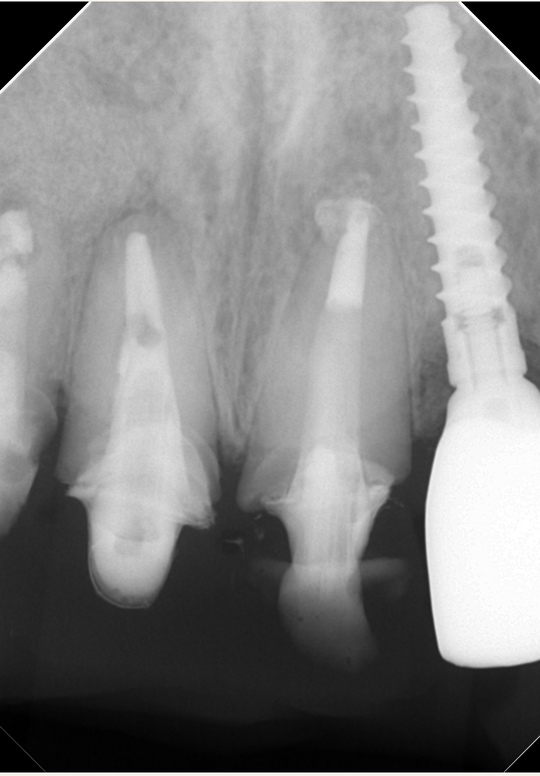

自費根管治療症例6 治療前(外科的歯内療法)

「前歯がなんとなく違和感がある」

以前の治療の切開の跡がわかります

インプラント隣の歯の根の先に人工材料が逸出しています。

右側(向かって左)の歯は以前、他院で外科的歯内療法を受けています

右側1番(真ん中)の歯は歯根破折のため抜歯になりました(コツ補填材を抜歯窩に充填)

2本とも歯根端切除術を行いました

外科的歯根端切除術逆根管充填(自費根管治療)、治療回数2回、治療期間約2週間、治療費6万8千円x2本 オールセラミクスクラウンブリッジ3本 17万円X3 単冠17万円X1

治療後

症状はすべて改善、経過1年後

外科的処置の跡はほとんどなく、ブリッジも自然な感じで歯がないようには見えません